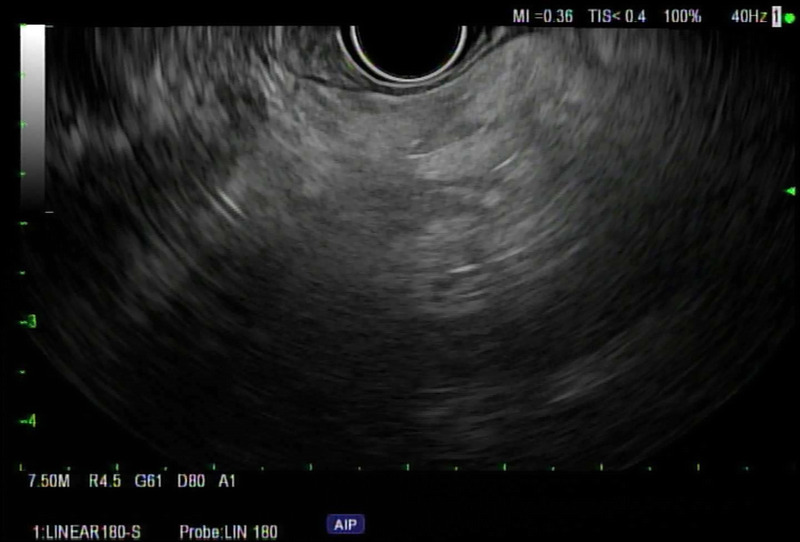

背景和目的:脂肪性胰腺(FP),传统上被认为是一种良性发现,最近由于越来越多的证据将其与各种疾病状态联系起来,包括胰腺癌(PC)的风险增加,因此一直受到密切关注。方法:回顾性研究2007年8月至2023年10月在单一机构接受EUS的患者,由一名具有25年以上经验的超声医师进行。针对在EUS期间确诊为FP的个体,我们将这些发现与EUS前后3个月或1年内进行的计算机断层扫描/磁共振成像(CT/MRI)的相应发现进行了比较。结果:纳入91例患者,并在EUS检查中确定为FP。高危患者中最常见的适应症是PC筛查(35.16%)。进行EUS检查时,65.93%的患者体重指数(BMI)≥30,63.73%的患者患有高血压,32.96%的患者患有2型糖尿病。在91例患者中,70例在EUS检查后3个月内进行了CT或MRI检查,仅有15例(21.43%)在影像学上报告了FP。91例患者1年内均行CT或MRI检查,影像学报告FP仅16例(17.58%)。结论:尽管EUS发现FP,但只有21.43%的患者在3个月内在CT/MRI上发现FP,这表明CT/MRI在识别FP方面的准确性低于EUS,或者在现实环境中可能漏报FP,即使在三级医疗中心也是如此。考虑到FP作为几种重要疾病和促进胰腺癌发生途径的潜在前体的作用,这种报道的差异值得注意。

Background and objectives: Fatty pancreas (FP), traditionally perceived as a benign finding, has been undergoing scrutiny lately due to growing evidence linking it to various disease states, including increased risk for pancreatic cancer (PC).

Methods: A retrospective study of patients who underwent EUS at a single institution from August 2007 to October 2023, conducted by one endosonographer with more than 25 years of experience. Focusing on individuals identified with FP during EUS, we compared these findings with corresponding findings on computed tomography/magnetic resonance imaging (CT/MRI) conducted within 3 months or 1 year prior to or following EUS.

Results: Ninety-one patients were included and identified as having FP on their EUS exams. The most common indication for EUS was PC screening in high-risk patients (35.16%). At the time of conducting EUS, 65.93% of patients had a body mass index (BMI) ≥30, 63.73% had hypertension, and 32.96% had type 2 diabetes mellitus (DM). Of the 91 patients, 70 had CT or MRI done within 3 months of the EUS date, and only 15 (21.43%) had FP reported on imaging. All 91 patients had CT or MRI within 1 year, and only 16 (17.58%) had FP reported on imaging.

Conclusion: Only 21.43% of patients had FP on their CT/MRI within 3 months despite EUS findings, suggesting either lower accuracy of CT/MRI compared to EUS in identifying FP or potential underreporting in a real-world setting, even in a tertiary care center. This discrepancy in reporting is noteworthy considering FP's role as a potential precursor to several important conditions and promoting pancreatic carcinogenesis pathways.